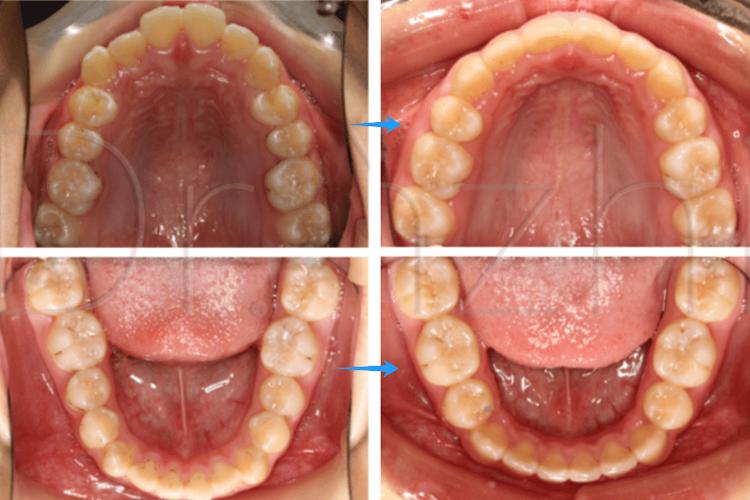

主动间隙关闭阶段(3-12个月,核心阶段)

此阶段通过矫治器(如滑动法关闭曲、种植支抗等)施加持续、轻柔的生物力,推动牙齿快速移动,前牙(切牙、尖牙)整体向远中移动,后牙(磨牙)向近中移动,同时保持垂直高度稳定,间隙变化图特征显著:前牙切端逐渐向拔牙侧移动,后牙近中面与对颌牙建立初步接触,间隙宽度每月缩小约1.0-1.5mm;牙槽骨改建活跃,压力侧可见骨吸收透射影,张力侧骨密度增高;牙根位置随牙齿移动调整,逐渐趋于平行。

精细调整阶段(12-18个月)

当间隙基本关闭后,进入细节优化阶段,医生通过调整弓丝转矩、更换细丝(如0.018英寸不锈钢丝)进行“轻力细调”,纠正牙齿的轻微扭转、转矩异常,建立稳定的咬合关系(如尖牙引导、组牙功能颌),间隙变化图显示:牙齿排列整齐,牙根平行,牙槽骨改建完成,密度均匀;牙龈形态逐渐恢复,若存在牙龈凹陷,可能需通过牙周手术或正畸牵引改善。